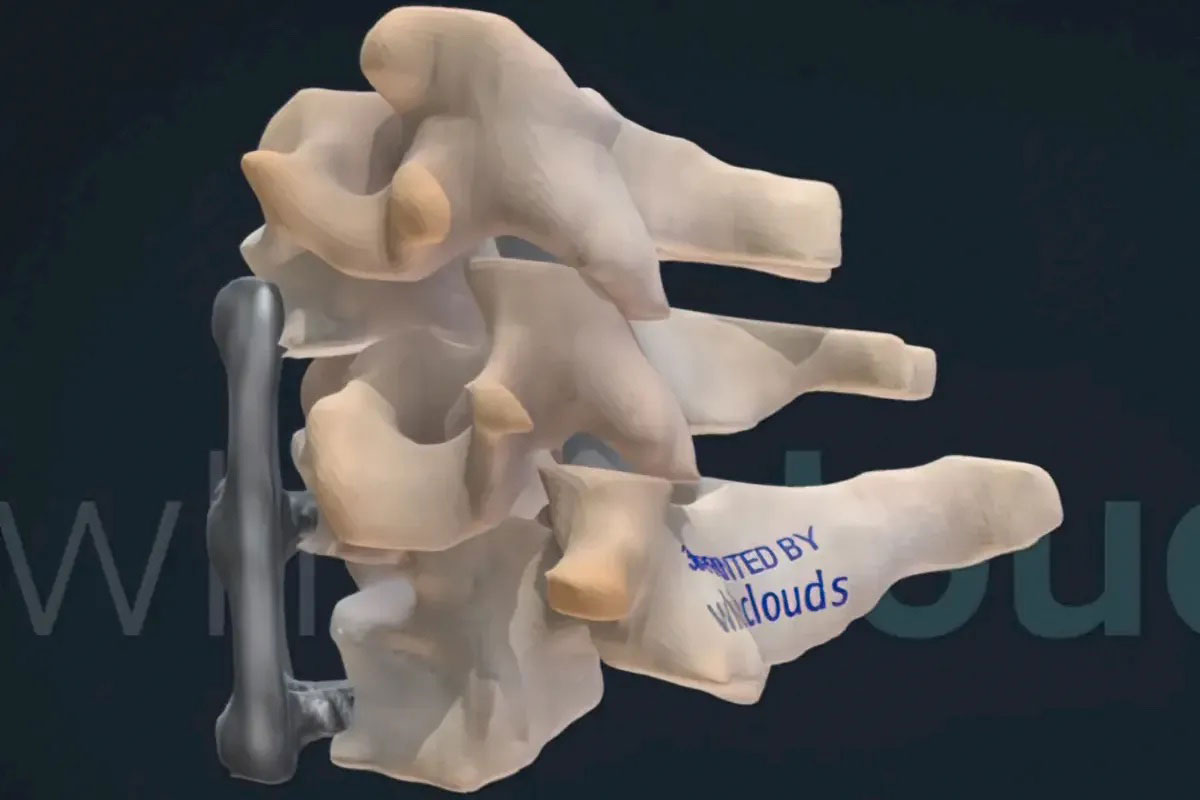

An attorney approached WhiteClouds to create a courtroom exhibit highlighting an area of his client’s spine. The client had undergone a surgery where the surgeon improperly attached hardware to his cervical spine. The surgical mistake caused the medical device to dig into the man’s esophagus. A trained medical professional could see the resulting damage in the medical imagery, but it was difficult for the attorney to get the jury to understand what the experts could. The true-to-life exhibit, created by WhiteClouds, brought a more in-depth understanding to the courtroom.